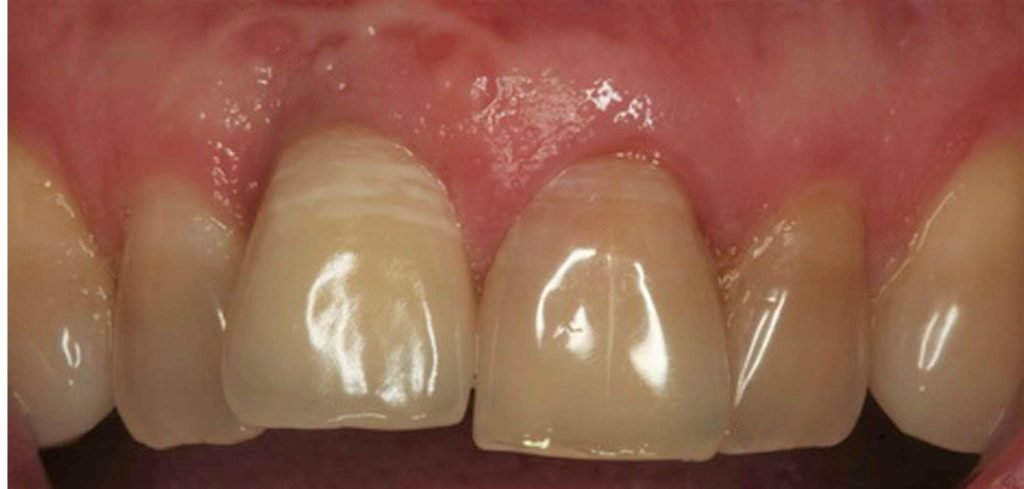

Implant Placement and Simultaneous Bone Grafting in the Aesthetic Zone